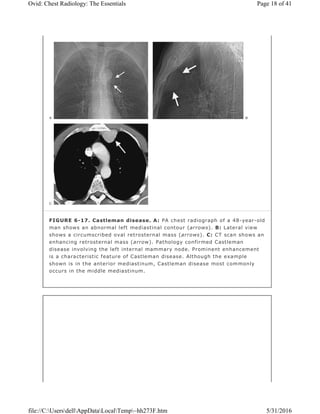

FIGURE 6-17. Castleman disease. A: PA chest radiograph of a 48-year-old

man shows an abnormal left mediastinal contour (arrows). B: Lateral view

shows a circumscribed oval retrosternal mass (arrows). C: CT scan shows an

enhancing retrosternal mass (arrow). Pathology confirmed Castleman

disease involving the left internal mammary node. Prominent enhancement

is a characteristic feature of Castleman disease. Although the example

shown is in the anterior mediastinum, Castleman disease most commonly

occurs in the middle mediastinum.